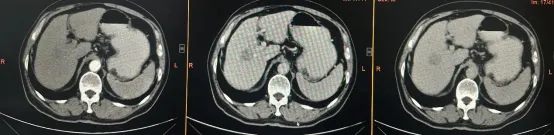

李大爷的肿瘤正好位于肝脏的Ⅴ、Ⅷ段交界处,紧邻门静脉的右前支与右后支分叉部,属于典型的、手术风险极高的中央型肝癌。

面对挑战,陈艳军主任医师团队进行了充分的术前规划和集体会诊,决定迎难而上,实施根治性切除手术。